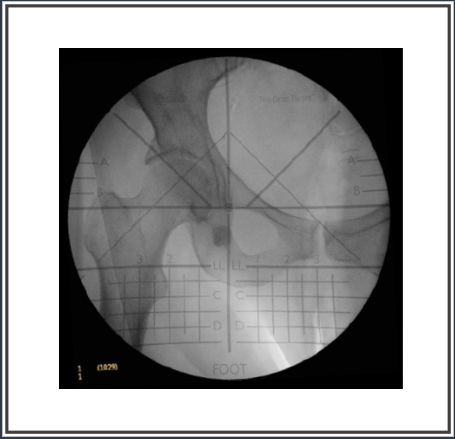

The all New HipGrid NINE is designed to be used with a 9″ C-arm when both lesser trochanters are not visible in the field of view and the surgeon desires to compare 2 AP hip views.

HipGrid NINE reveals fluoroscopic distortion and utilizes the TearDrop Target™ surgical technique to enhance intra-operative decisions when determining:

• Pelvic Pitch

• Pelvic Obliquity

• Acetabular Cup Position

• Hip Offset

• Leg Length Restoration

To meet the need for practical, cost-effective solutions for outpatient orthopedic surgery patients, OrthoGrid is pleased to introduce the new HipGrid NINE. Developed using the same patented methods and designs as the original HipGrid, the 9″ System features distortion-revealing grids that make it simple and easy for physicians to immediately make informed intra-operative decisions on Pelvic Pitch™, Pelvic Obliquity, Acetabular Cup Position, Hip Offset and Leg Length Restoration.